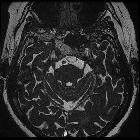

MRI

A stalk-like connection to the clivus is usually seen if high-resolution images are obtained.

Apart from the characteristic location (retroclival, prepontine, and intradural), MRI findings are non-specific, with signal similar to CSF:

- T1: hypointense

- T2: hyperintense

- T1 C+ (Gd): variable, however, most cases have not shown substantial enhancement